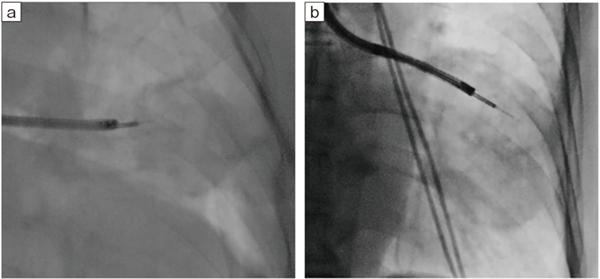

図15 Cアームを活用したクライオ生検1

被検者を動かさずに行えるため、安全性が向上する(Accent適用症例画像)。

Cアームを活用したクライオ生検

Ultimax-iのCアームは、クライオ生検時に有用である。クライオ生検では、胸膜から1cm手前の位置が最も良質かつ安全に検体を採取できるとされており1)、そこでいかに確実に採取を行うかが重要なポイントとなる。生検中に介助者らが被検者の体位を変換し、保持している間に体が動いてしまうケースがあるが、Cアームを用いることで、被検者の体位を固定したまま最適な角度で検体採取が行える。前医が気管支肺胞洗浄(BAL)や経気管支肺生検(TBLB)を行ったが診断がつかず、当院でCアームを用いてクライオ生検を行った結果、肺胞蛋白症と診断された症例なども経験している(図15、16)。Cアームを有効に活用することで、病変やデバイスと胸膜との位置関係をより正確に把握し、安全に検査を行えることは、大きなメリットとなる。